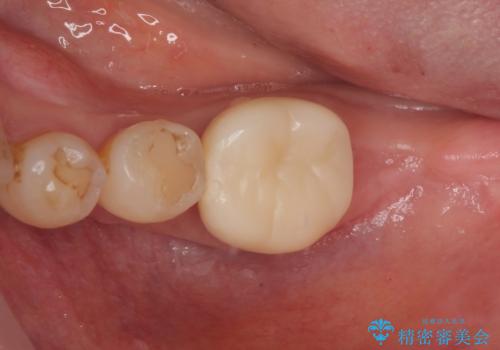

骨よりも深く進行したむし歯 即時荷重インプラントでの短期間治療

- 左下奥のクラウンに違和感を感じるとのことで来院された患者様です。

最後方歯は歯槽骨よりも深い部分にまでむし歯が及んでおり、患者様と相談の上、インプラントによる補綴治療を行うこととしました。

手前の歯は、適合の悪いクラウンを最後方歯と同時にオールセラミッククラウンにて補綴治療を行うこととしました。

骨の高さが不十分であったため、インプラント強度を維持しながらも高さの小さいインプランを使用しました。